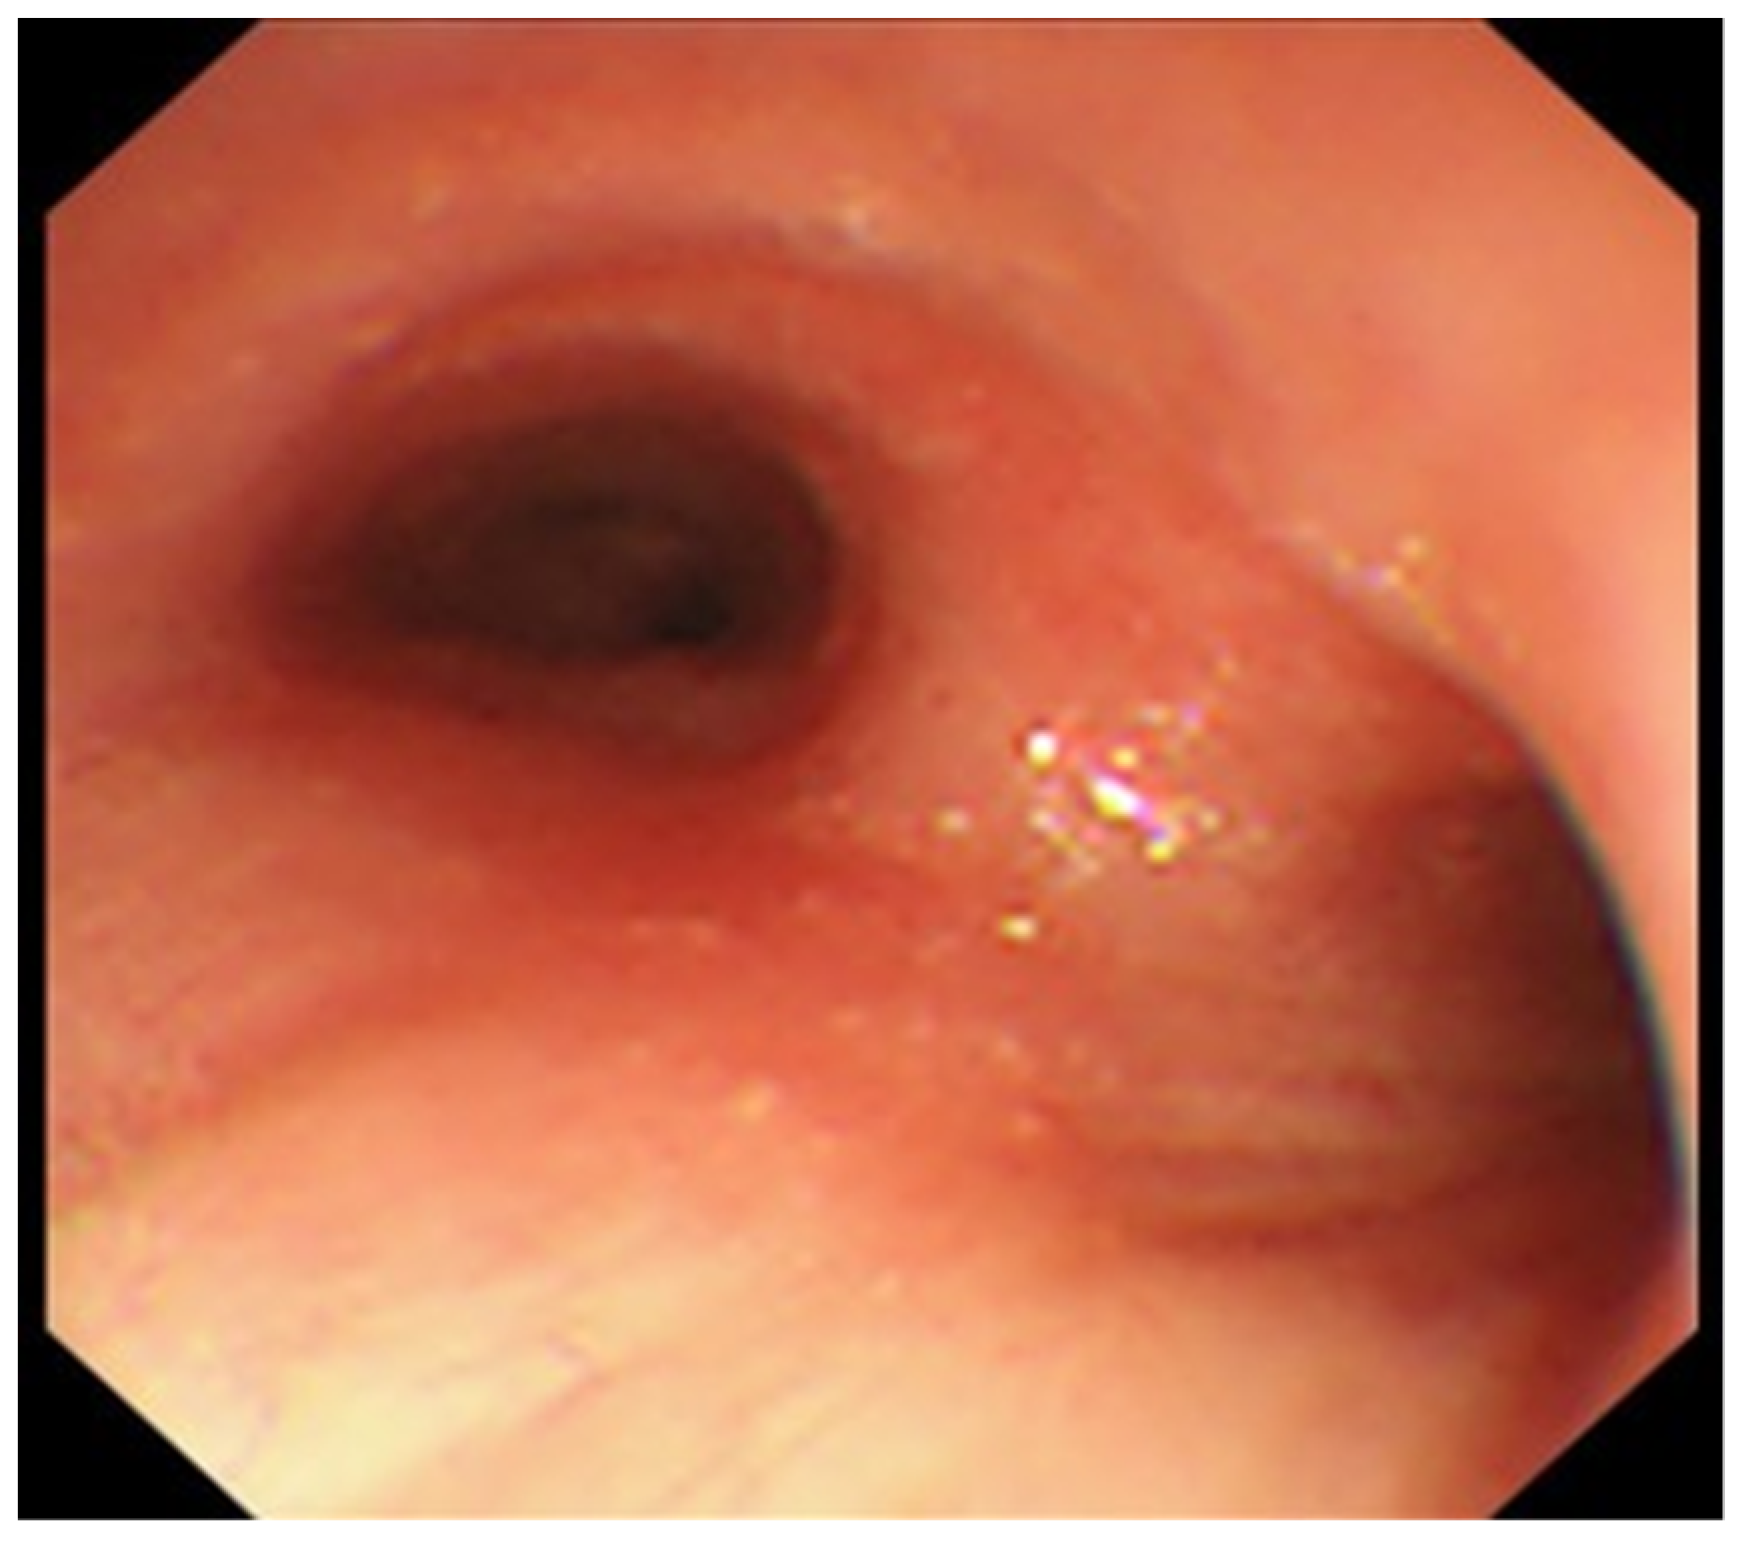

2. Case